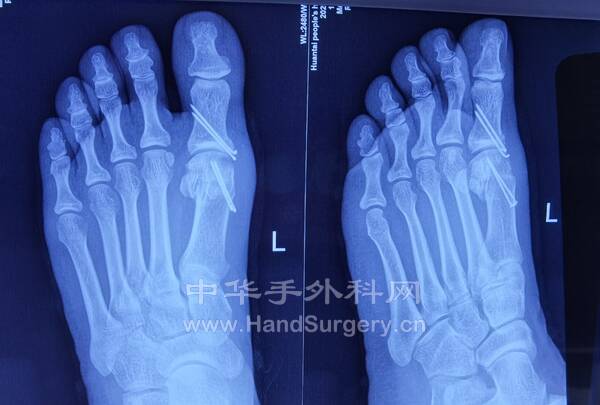

1.喧嚣的省立医院中心院区门诊2.老师做的拇外翻患者术后5周复查

3.外院手术治疗1.5个月的患者,患者非常年轻!